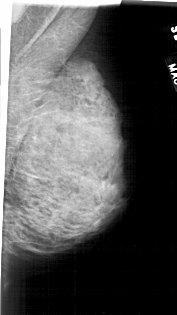

A_1939_1.RIGHT_MLO

RIGHT_MLO LINES 4711 PIXELS_PER_LINE 2641 BITS_PER_PIXEL 12 RESOLUTION 43.5 NON_OVERLAY